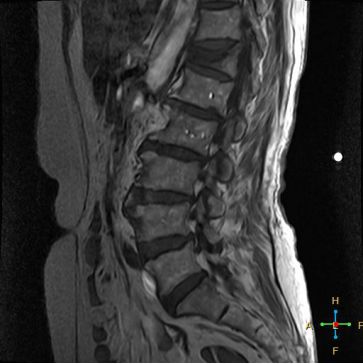

2 良性压缩性骨折 椎体形态:楔形、凹陷形。 椎体连续性病变(骨质疏松):新鲜、陈旧骨折并存。

椎间盘改变:椎间盘增厚呈双凸透镜状, 椎间盘疝入椎体, 形成许莫氏结节。

椎体后上角或后下角向后翘起, 呈尖突样突入椎管, 具有特异性,为其它原因的骨折所少见。

——良性压缩性骨折MR信号特点—— 良性骨折的修复过程:缺血性变化--修复(骨髓水肿、血流增加或充血现象)--修复近完成(血流恢复正常)--慢性期(脂肪组织再生)。 正常成人:椎体为黄骨髓,T1WI 、T2WI 均为高信号。 当骨髓内出现水肿时,T1 低信号, 与残余的正常骨髓形成明显对比,所以椎体压缩骨折后,MR 信号改变以 T1WI 上观察最好;而在常规 T2WI 图像上,病变骨髓的长 T2 高信号与正常骨髓脂肪信号差别较小,不易观察;T2WI 脂肪抑制技术对于突出显示骨折区长 T2 组织信号具有独特优势,对于判断椎体是否发生脂肪变及骨折是否愈合也有一定价值。 急性早期,椎体压缩,局部缺血,骨髓水肿,T1WI 不均匀低信号,T2WI 高信号,增强扫描无明显的强化。 随后,骨折部位开始修复,血流量增加,增强扫描可出现明显的强化,平扫信号无改变。 慢性期,骨髓内脂肪组织再生,T1WI 椎体内呈混杂高信号。

由于大多数外力轻微,椎体内多形成范围局限、移位不明显的骨折线,骨折线周围水肿亦多局限,因此,较少出现全椎体信号异常。

椎体后角回避现象:T1WI 椎体上部或大部呈低信号, 而后角信号不变。

椎弓根改变:由于旋转的扭力或是上下的压力造成椎体血流循环改变而致椎弓根的髓内水肿,使信号改变累及椎弓根,但椎弓根无变形或膨大。

所以,椎弓根的信号改变并非恶性骨肿瘤所特有,约20%~ 30%的良性压缩性骨折会出现椎弓根水肿而信号增高。 恶性压缩性骨折, 约有60%~ 80%出现椎弓根水肿及信号变化,而在椎弓根出现不正常信号的恶性压缩性骨折中, 约有50%~70%出现椎弓根膨大的现象,为其特异性, 可作为鉴别诊断的依据。 椎旁软组织肿块:最典型的表现为椎旁一薄环状异常信号带,因为椎体压缩时常继发椎旁软组织水肿与出血, 这一征象多见于单纯骨折, 病理性骨折少见。

4 总结:鉴别诊断 ——良性压缩性骨折—— 楔形或凹陷形 连续性分布 椎间盘增厚双凸状,许莫氏结节 急性期T1WI不均匀低信号 椎体后角翘起突入椎管内 椎体后角回避现象 可伴椎弓根水肿、无膨大 椎旁薄环形软组织影